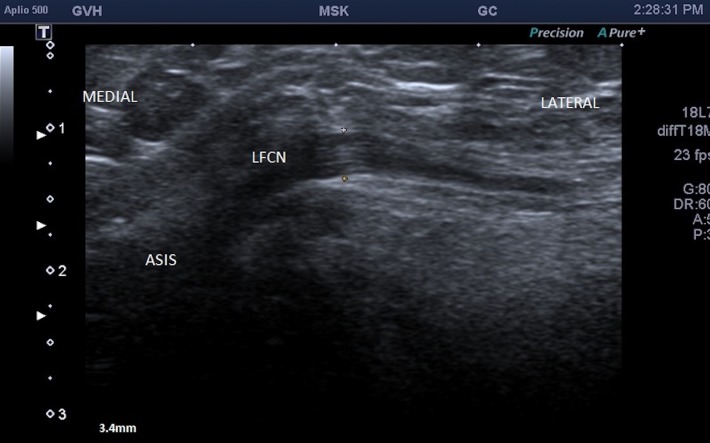

Eight weeks following initial presentation, a focal ultrasound of the groin and left thigh was performed which revealed a thickened and abnormally hypoechoic left lateral femoral cutaneous nerve, measuring 3.4 mm in diameter (figures 1 and 2) compared with 2.2 mm on the right side (figure 3). There was loss of the normal fascicular pattern between the anterior superior iliac spine and the inguinal ligament, consistent with nerve entrapment. At this point, the diagnosis of left meralgia paraesthetica was made.

Figure 1.

Ultrasound image demonstrating a thickened and abnormally hypoechoic left lateral femoral cutaneous nerve (LFCN).